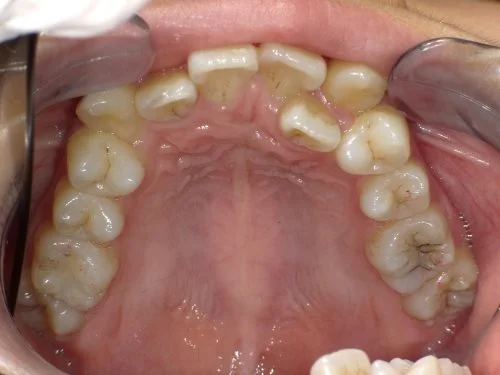

<症例7>歯がガタガタで噛み合わせが悪くお悩み

抜歯無し・マウスピースのみで矯正した症例です。

もともと歯列弓が非常に狭く、V字に近い形をしていたので噛み合わせも非常に不安定でした。

また、下顎前歯部がかなり上の方に生えていたため、下の前歯が上の前歯を突き上げてしまい出っ歯の状態になっていました。

現在では見た目はもちろん、臼歯の噛み合わせも改善しております。

患者様と症状

主訴:歯のガタガタ、噛み合わせが悪い

性別・年齢:20代女性

問題点:叢生(重度)、V字歯列弓、ディープバイト

診断:前歯部の叢生を伴うアングルⅠ級、骨格性Ⅰ級の不正咬合

主なリスク:臼歯の移動に伴い一時的に咬合しにくくなる、歯肉退縮

症状:叢生(そうせい) 過蓋咬合(かがいこうごう)

治療内容

治療期間:1年10ヶ月

治療費用:990,000円(税込)

プラン:Full2プラン

抜歯:無し

治療前後の写真